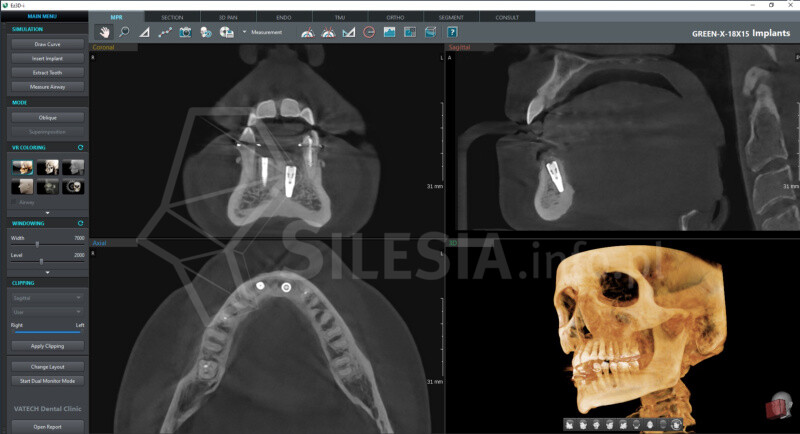

Pracownia wyposażona jest w tomograf stożkowy Vatech Green X (model 2025) – najnowszej generacji urządzenie, które łączy najwyższą jakość obrazów 2D i 3D z minimalną dawką promieniowania.

Badania są w pełni bezpieczne także dla dzieci i osób, które muszą wykonywać je regularnie.

Skanowanie trwa zaledwie 2,9 sekundy, a technologia AI automatycznie redukuje zakłócenia i poprawia ostrość zdjęć.

Specjalny tryb Endo pozwala uzyskać obraz kanałów zębowych w najwyższej rozdzielczości – idealny w diagnostyce endodontycznej.

CBCT (tomografia stożkowa) to nowoczesne badanie 3D, które pokazuje zęby, kości, zatoki i stawy skroniowo-żuchwowe w pełnym trójwymiarze. Umożliwia bardzo dokładne zaplanowanie leczenia chirurgicznego, ortodontycznego, implantologicznego i laryngologicznego.